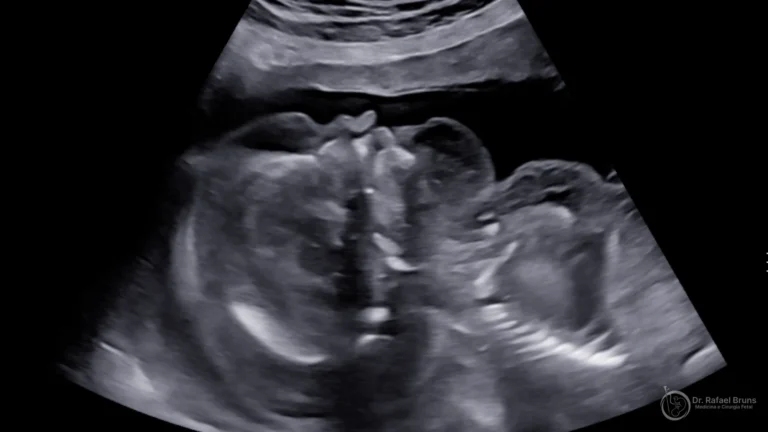

Hidropisia fetal: a complicação mais grave da anemia não tratada

A hidropisia fetal é a manifestação mais grave da anemia não tratada. Caracteriza-se pelo acúmulo anormal de líquido em dois ou mais compartimentos fetais: cavidade pleural, pericárdio, cavidade peritoneal ou edema subcutâneo difuso.

Quando a hidropisia está presente no momento do diagnóstico, o prognóstico é mais reservado — mas não necessariamente sem saída. Fetos com hidropisia que recebem transfusão intrauterina ainda têm chance real de sobrevida, embora menor do que aqueles tratados antes da instalação do quadro. Isso reforça a importância do diagnóstico precoce e do acompanhamento regular em gestações de risco.

- Ultrassom mostrando ascite, derrame pleural ou edema generalizado no feto